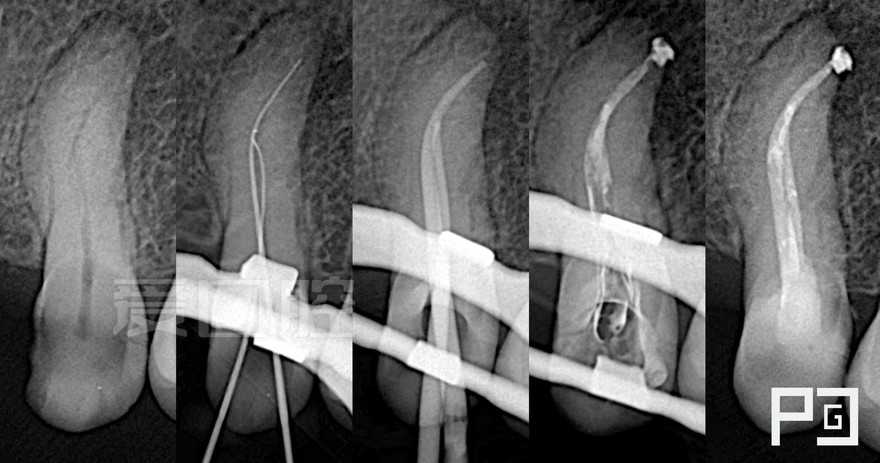

看个根充 —— 上5

by Paco CG